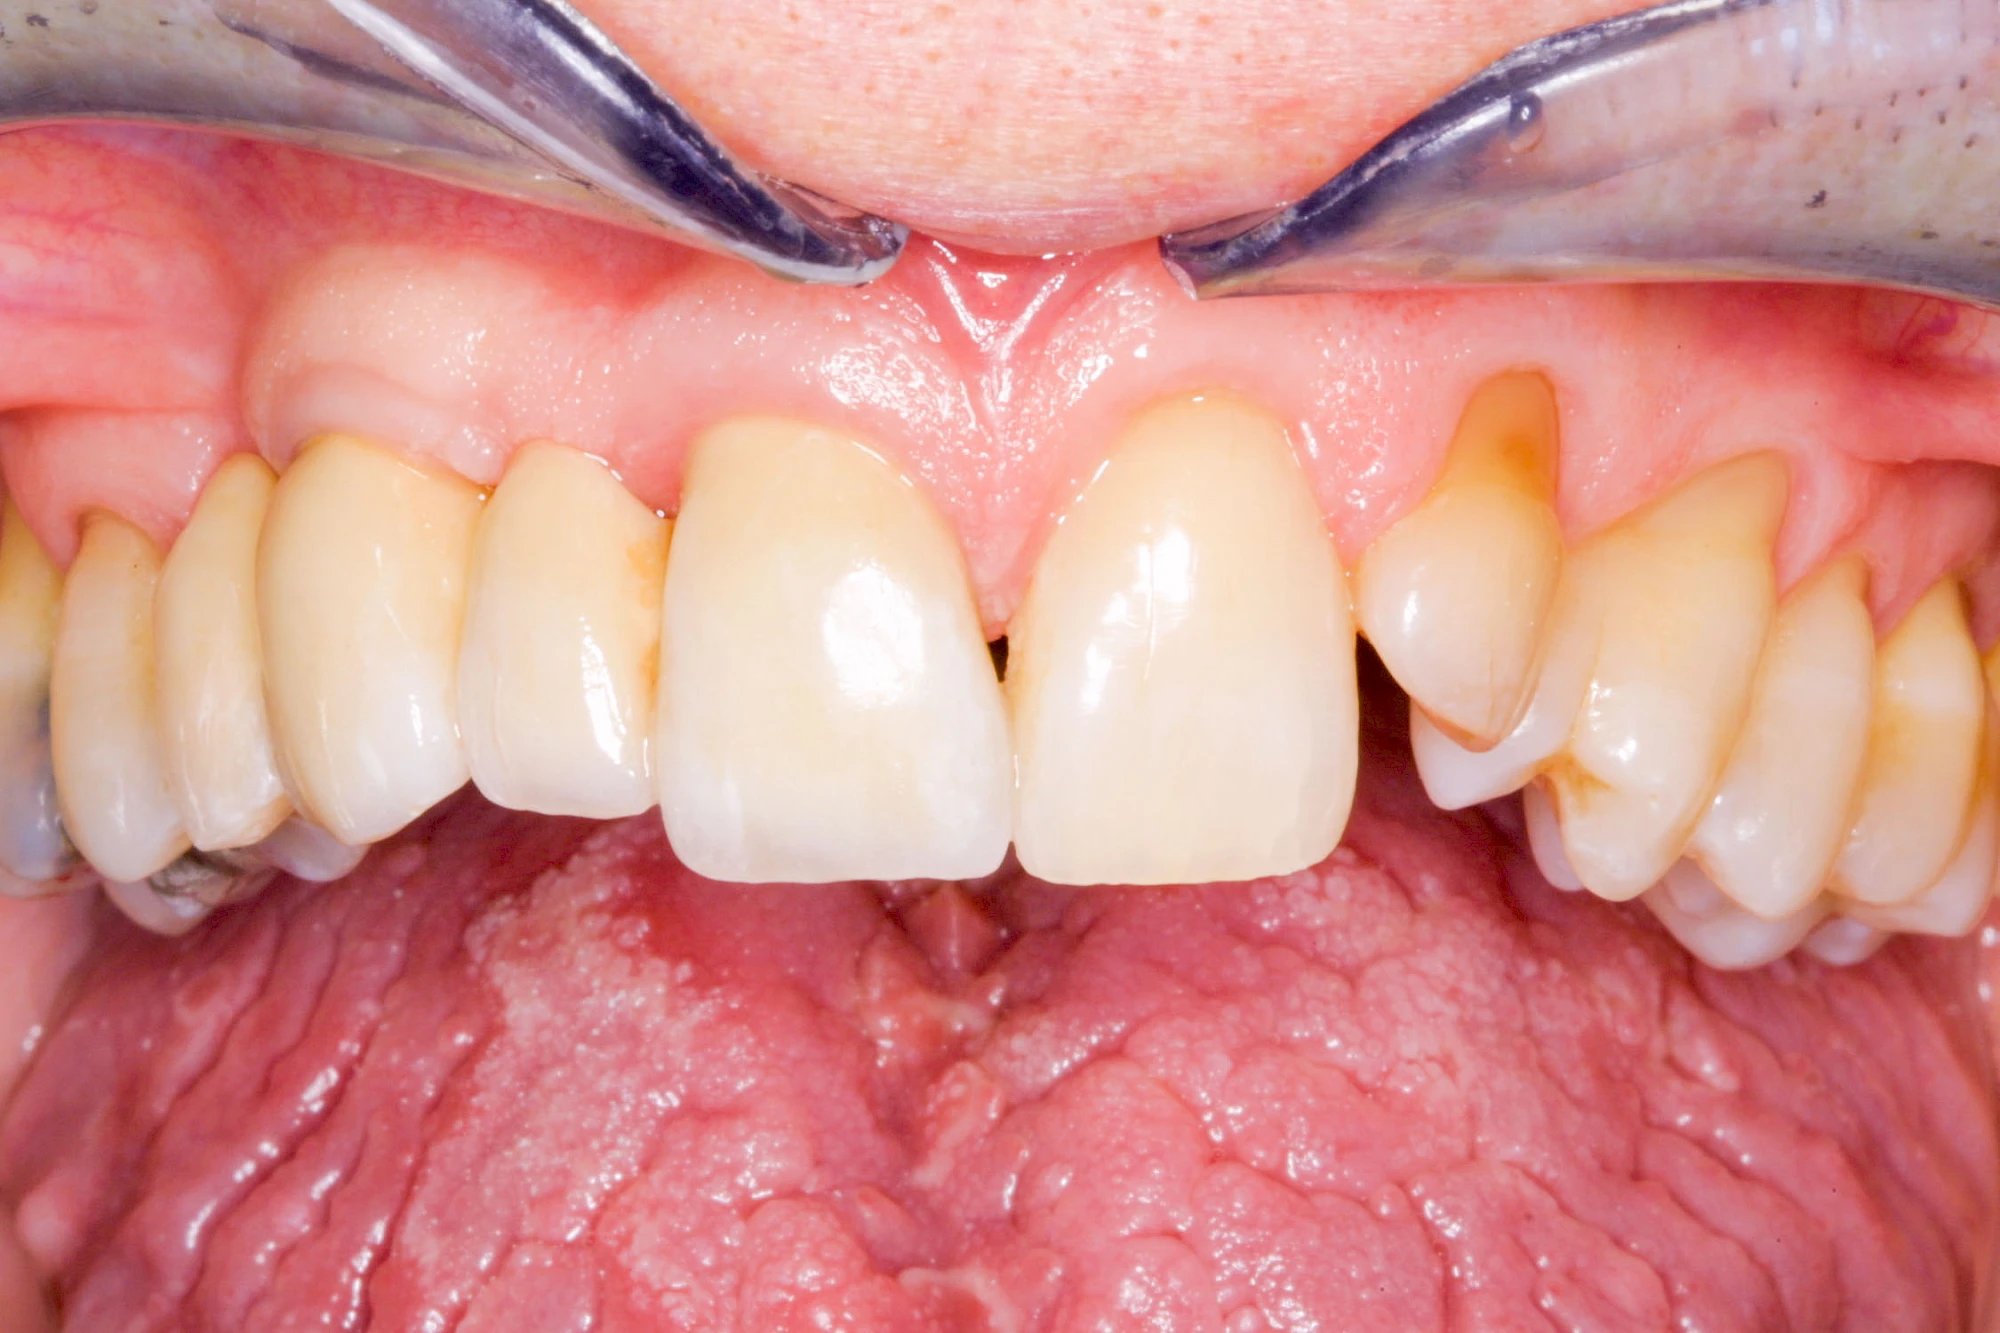

Fehlen einzelne Zähne und die Nachbarzähne sind unbeschadet oder gut zahnärztlich versorgt, werden immer häufiger Implantate gewählt, um die Lücken zu schließen. Auch bei größeren oder verteilten Lücken, wenn keine herausnehmbare Prothese gewünscht ist, werden Implantate für Kronen- bzw. Brückenversorgungen gesetzt. In Einzelfällen entscheiden sich sogar zahnlose Patienten für eine festsitzende Versorgung auf Implantaten.

Varianten zur Verankerung von festsitzendem Zahnersatz auf Implantaten